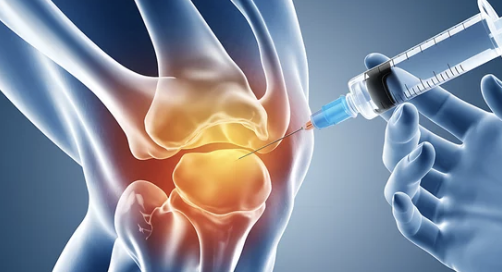

✅ 4) 수술 진행 & 지원금 지급

✔ 선정 통보 후 3개월 이내에 수술을 받아야 함

✔ 지원금은 병원으로 직접 지급되며, 환자는 본인 부담금만 지불하면 됨